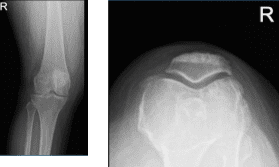

She presented her Xray results, for her left knee there are mild osteoarthritic degenerative changes. For the right knee, there are moderate osteoarthritic degenerative changes. There are no fractures and there are no acute fractures.

Right knee X-ray